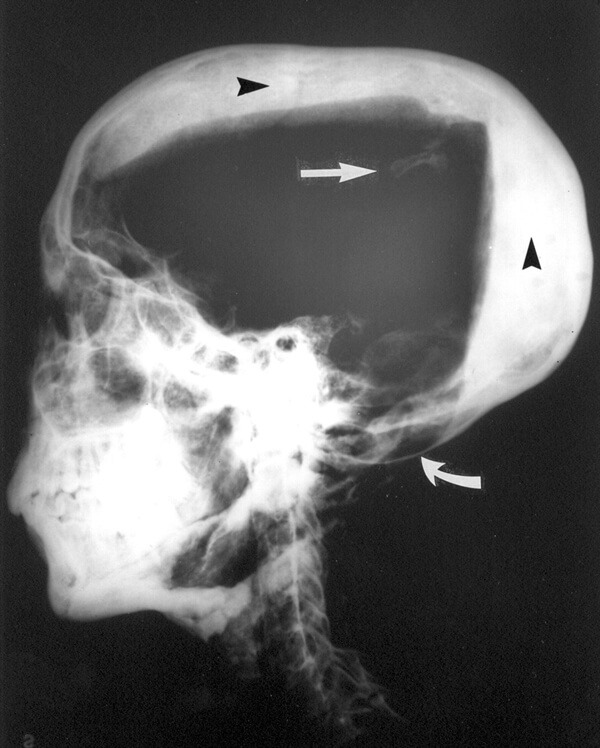

원한 없는 저주는 없기에, 투탕카멘의 저주인 ‘파라오의 저주’는 실체를 해부할 필요가 있다. 투탕카멘 무덤의 발굴 당시 미라의 X선을 촬영한 결과, 머리에 둔기를 맞은 듯한 두개골 골절이 발견되어 투탕카멘이 암살을 당했다는 설이 설득력 있게 주장되었다. 실제 고대 이집트 역사에 따르면 투탕카멘이 죽은 뒤로 의문투성이의 왕위 계승이 일어나기도 했다. 이를 통해 일부 고고학자들은 투탕카멘의 죽음을 ‘왕위를 노린 자에 의한 살인’으로 정의하고 있다.

투탕카멘이 살해당한 것이 아니라는 반박설도 유력하다. 투탕카멘의 미라 X선 촬영 이후 밝혀진 또 다른 사실에 의하면, 투탕카멘은 살해로 인해 죽은 것이 아닌 다리의 심각한 골절이 상처로 덧나 죽은 것이라는 주장이 있다. 항생제라는 개념이 없었던 고대 이집트 당시에는 이러한 상처가 곪고 덧나 죽는 경우가 상당히 많았다는 설이 있기 때문이다. 한편으로는 투탕카멘의 부친이 유전적 기형 의혹을 받고 있어 유전병으로 인해 오래 재위하지 못하고 병사했다는 시각도 나온다.